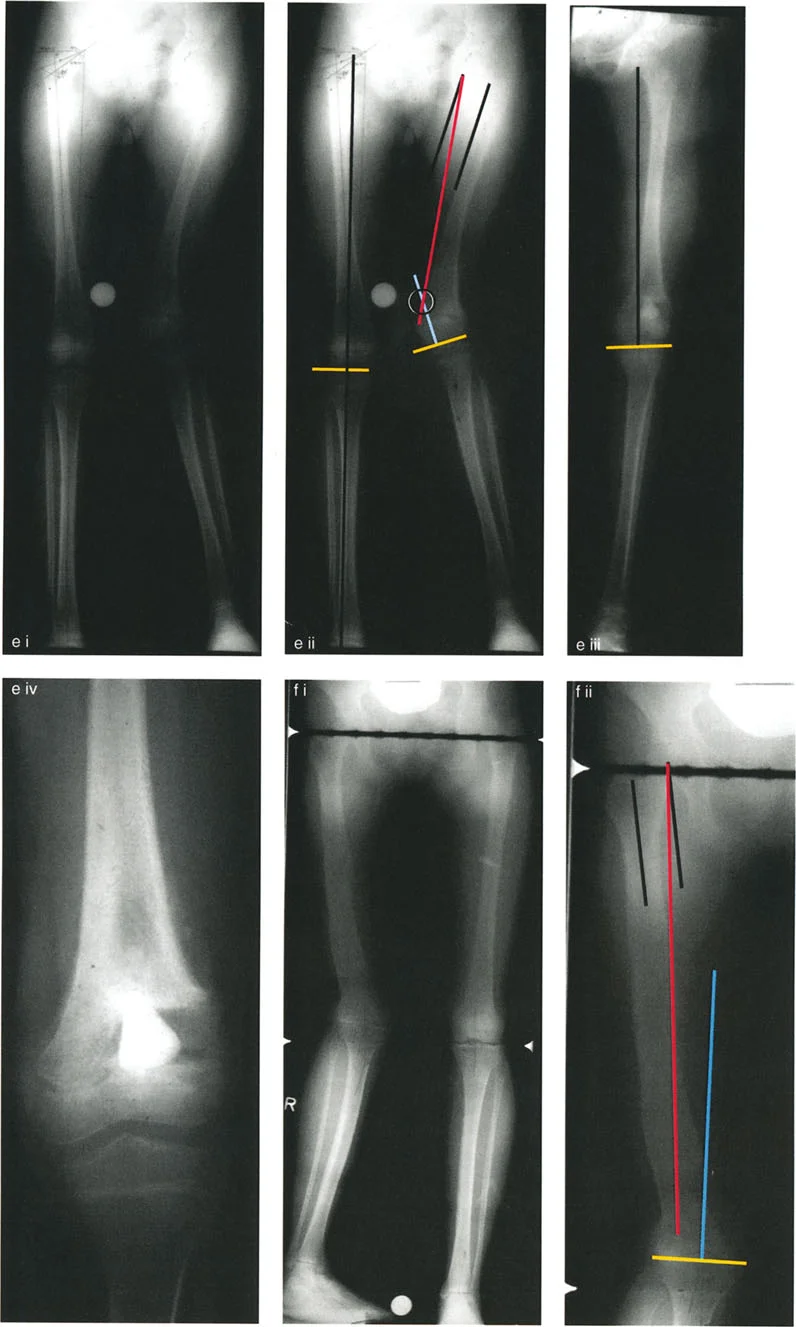

* الأشعة السينية الطويلة للطرف السفلي (Full-Length Standing Radiographs): هذه الأشعة هي الأكثر أهمية. يتم التقاطها والمريض واقفًا، مما يسمح بتقييم المحاور الميكانيكية للطرف تحت وزن الجسم. يقوم الدكتور هطيف بتحليل هذه الصور بدقة لرسم:

* المحور الميكانيكي: الخط الذي يمتد من مركز رأس الفخذ إلى مركز الكاحل، ومروره بالنسبة لمركز الركبة.

* المحور التشريحي: الخط الذي يمر عبر منتصف العظم نفسه.

* زوايا توجيه المفاصل: مثل mLDFA و MPTA و LPFA لتحديد مكان التشوه (في الفخذ أو الساق).

* مركز دوران الانحراف (CORA): وهو النقطة التي يتقاطع فيها المحوران الميكانيكيان القريب والبعيد، والتي تمثل قمة التشوه.

من خلال هذه الفحوصات الدقيقة، يتمكن الأستاذ الدكتور محمد هطيف من بناء "خريطة" مفصلة للتشوه، مما يسمح له بتحديد أفضل استراتيجية جراحية لتحقيق تصحيح مثالي وفقًا لمبادئ الدكتور بالي.